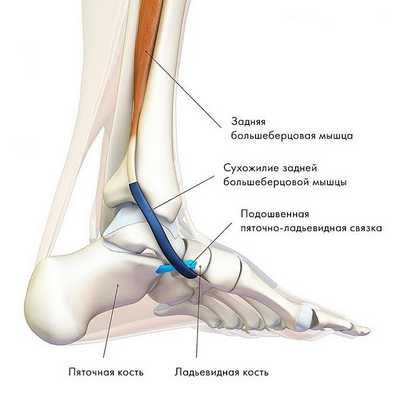

2. Заднее большеберцовое мышечное образование, берущее начало в районе малоберцовой и большеберцовой костей и, с другой стороны, прикрепленное к ладьевидной кости, отвечает за инверсию стопы, ее сгибание в голеностопе и (ключевая функция) стабилизацию ее свода.

Сокращаясь в процессе бега или ходьбы, данная мышца осуществляет блокировку сустава стопы, заставляя ее работать подобно жесткому рычагу. При этом, травмирование, перерастяжение, либо разрыв сухожилия задней большеберцовой мышцы провоцирует развитие такого широко распространенного недуга, как плоскостопие.

Рис. Сухожилие задней большеберцовой мышцы (ЗБМ).

Задняя большеберцовая мышца активна в течение фазы опоры, включается сразу после контакта пятки с опорой и быстро прекращает сокращаться после поднятия пятки. Ее брюшко начинается глубоко внутри задней части нижней конечности, сухожилие следует вниз до задней части медиальной лодыжки, где находится кпереди от сухожилия длинного сгибателя пальцев, заднего большеберцового нейрососудистого пучка (задняя б/б артерия, вена и нерв) и сухожилия сгибателя большого пальца. Все эти структуры ограничиваются удерживателем сгибателей возле медиальной лодыжки. Сухожилие задней б/б мышцы проходит в борозде позади и ниже медиальной лодыжки, разделяясь на 3 части у медиальной стороны тарана. Передняя часть прикрепляется к бугристости ладьевидной кости, средняя часть продолжается в плантарную тарзальную область и прикрепляется к плантарной части клиновидных костей, кубовидной и в основании 2, 3 и 4 метатарзальных костей. Задняя часть внедряется как пучок в переднюю часть нижней пяточно-ладьевидной связки. Медиальная лодыжка работает как многороликовый блок, позволяя сухожилию задней б/б мышцы изменять направление тяги, и эти точки прикрепления обеспечивают супинацию заднего и среднего отделов стопы во время переноса веса, в то время как происходит стабилизация арочной конструкции среднего отдела.

Главная функция задней б/б мышцы - добиться супинации в подтаранном суставе и приведения переднего отдела стопы вокруг косой оси среднеплюсневого сустава.